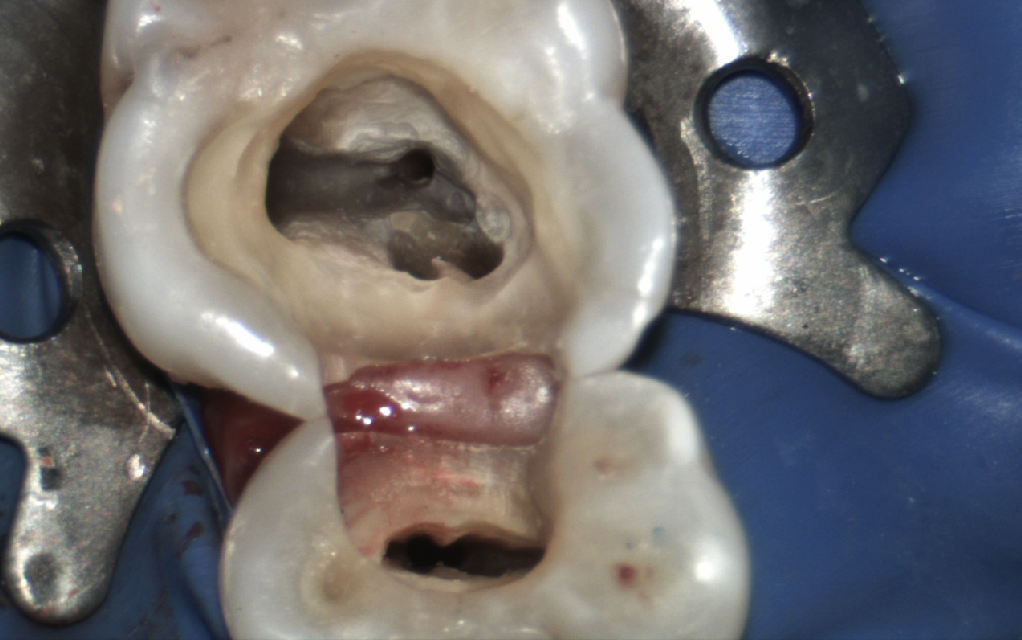

Endodontics